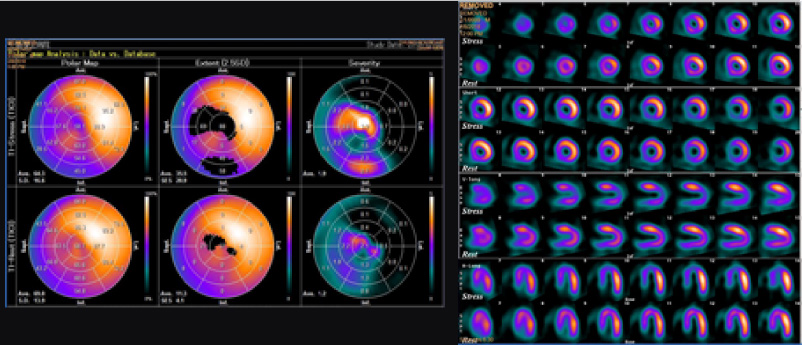

RI(核医学検査)

RI検査(核医学検査)は、ごく微量の放射性物質(ラジオアイソトープ:RI)を含む薬を用いて病気を診断する検査です。この放射性医薬品を注射、吸入などにより体内に取り込みます。体内に取り込まれると、特定の臓器(骨や腫瘍など)に集まりそこから放出される放射線(γ線)をガンマカメラで測定し、その分布を画像化します。

この検査の特徴は臓器の位置や大きさの他に機能が分かるというところです。

検査の種類

心筋血流シンチ 脳血流シンチ 骨シンチ 甲状腺シンチ 腫瘍シンチなど

狭心症

心筋シンチ

【当院では心筋シンチと脳血流シンチに特に力を入れています】